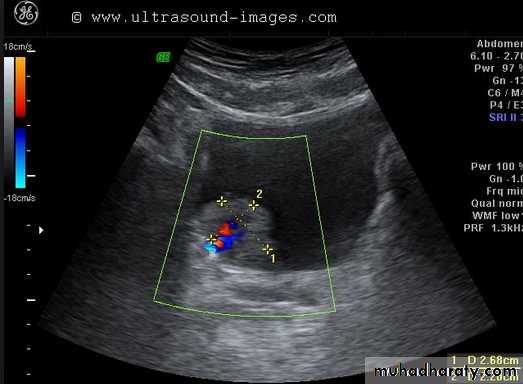

Duplex ultrasound scanners that combined both functions , thus allowing the imaging of anatomy and the measurement of blood flow with one single instrument, soon followed .

Vascular ultrasound (Doppler)

. It can yield blood flow information by applying the Doppler principle .